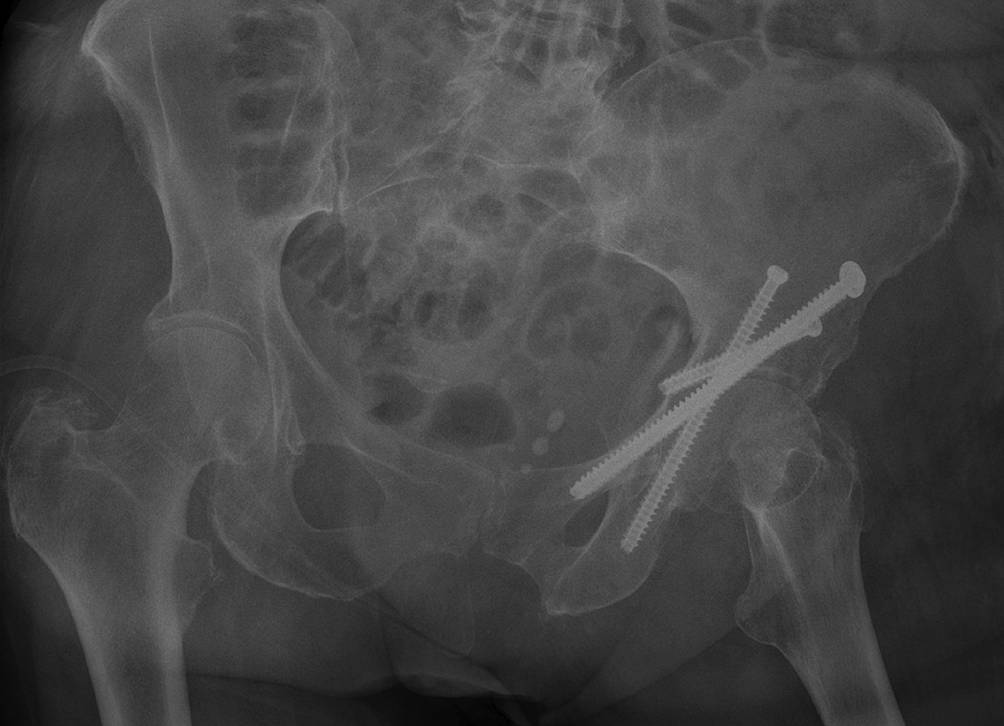

Abb. 12

Das intraoperative Bild nach Schraubenimplantation zeigt die korrekte Schraubenlage bei Fixierung aller Fragmente. Eine intraartikuläre Lage der Schrauben kann im Röntgenbild nicht suffizient ausgeschlossen werden, weshalb dies bereits im intraoperativen 3‑D-Scan durchgeführt wird

• Wir empfehlen die radiologischen Kontrollen nach 6 Wochen (Abb. 13), 3 Monaten und nach 12 Monaten.

Abb. 13

Die Kontrolle nach 6 Wochen dokumentiert die korrekte Lage der Schrauben ohne eine sekundäre Dislokation. Die Patientin kann sich bereits selbstständig wieder am Rollator unter Vollbelastung des linken Beines mobilisieren